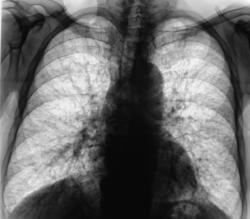

Весьма часто получая заключение из соответствующего учреждения - "Данных за туберкулёз нет", возникает вопрос - "А что есть"? Или фтизиатры перестают быть пульмонологами?

Пациент после расшифровки флюорограмм "был взят на контроль". Проведено дообследование.

Валентин Львович! Все таки нужен анамнез. Есть ли у пациента в анамнезе профвредность (шахтер, производство цемента и т.д.). На мой взгляд картина сходна с двумя заболеваниями: силикотуберкулез и легочной фиброз Хаммена-Рича.

Профвредности никакой, разве, что раньше была очень вредная жена, житель сельской местности. Я думал о синдроме Хаммана-Рича. Вчера - кровохарканье.

Валентин Львович. Если учесть те крохи  анамнеза, которые  вы предоставили  я склоняюсь к  обострению  хронического бронхита.  А  вообще по  фтизитрам  вы  правы -  они  "берут"  от нас пациента только с  раскрученным  диагнозом. Даже  не смотря на  явные  признаки  ТБЦ по рентгенограмме.

Интересно а с какими жалобами он поступил?и сколько они его беспокоят(я начинающий пульмонолог).Если не ошибаюсь картина сотового легкого.Возможно ИФА,легкое фермера?